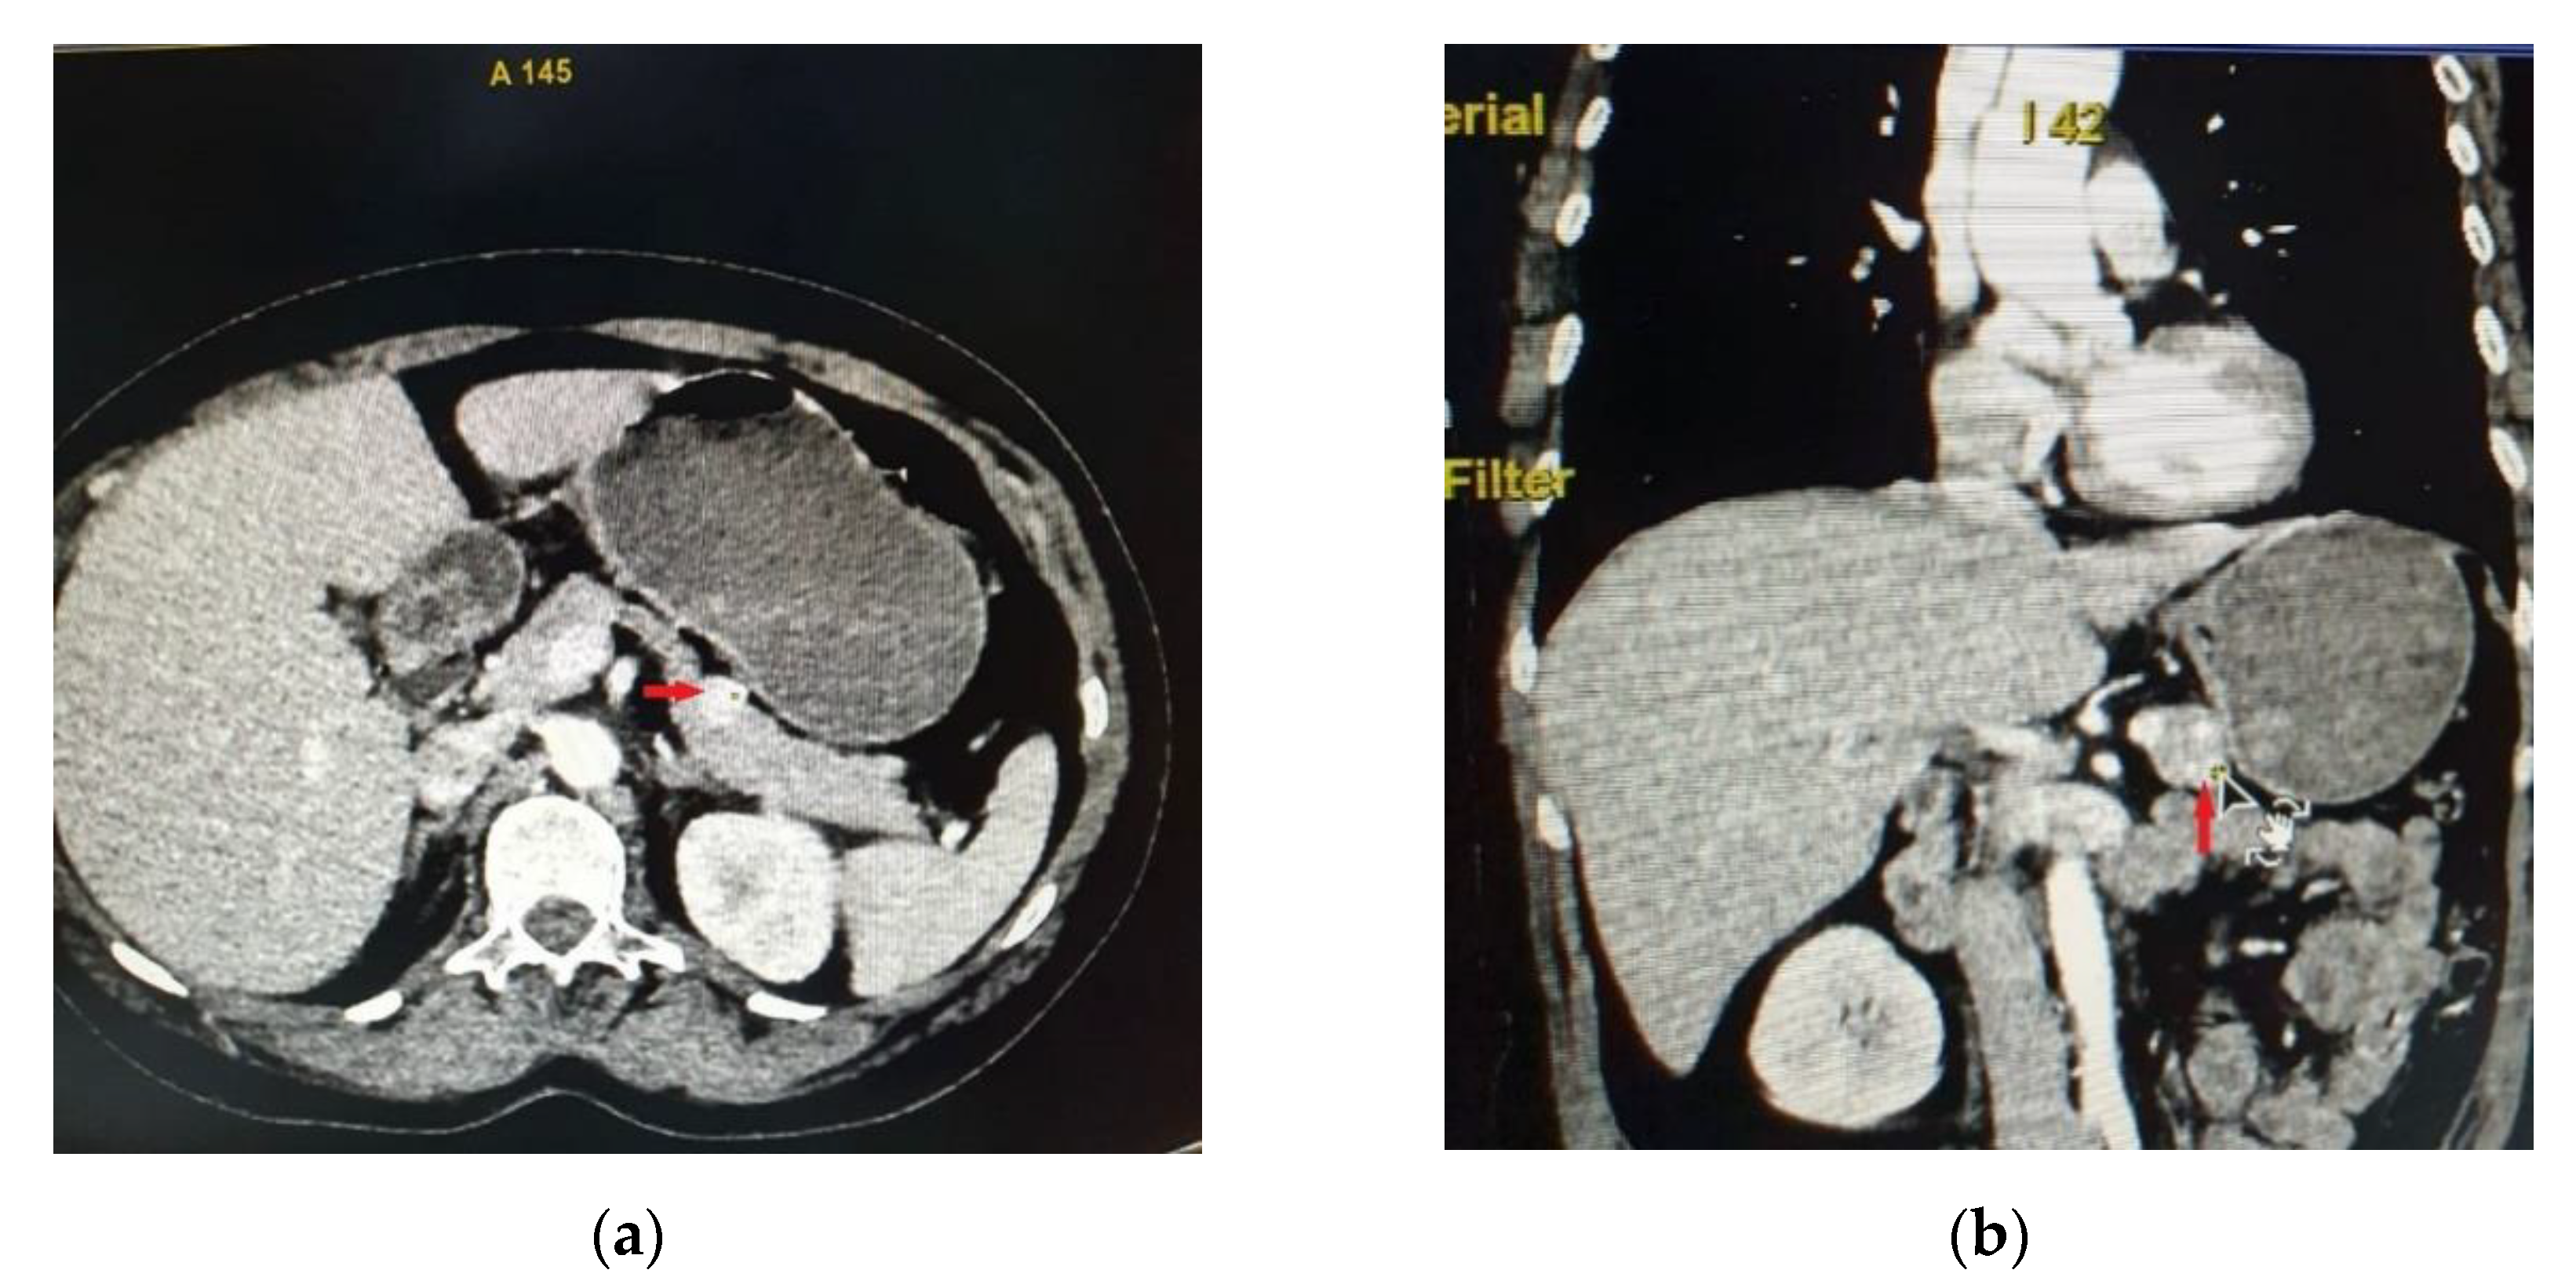

Abdominal CT showed in the anterior part of the pancreatic corporeo-caudal region an isodense rounded tumor measuring 15.3/15 mm, with intense iodophilia that is maintained in the venous phase (Figure 1). A complementary abdominal magnetic resonance imaging (MRI) was performed, indicating a pancreatic hypervascular tumor that appeared with hypo/isosignal at T1- weighted sequences and slightly hypersignal at T2- weighted sequences, homogeneous in the post-contrast study, with diffusion restrictions in diffusion-weighted imaging sequences correlated with apparent diffusion coefficient maps.

Figure 1. Abdominal CT - axial section (a) and coronal section (b) - indicating in the anterior part of the pancreatic corporeo-caudal region an isodense tumor measuring 15.3/15 mm, with intense iodophilia.